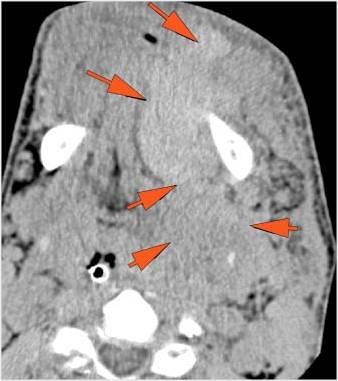

Facial and Scalp Soft Tissues and Airway

There is localized edema, hematoma or abscess within in the facial or scalp soft tissues, SMAS, infratemporal fossa, masticator space or oral cavity. [Yes/No]

There is evidence of gas or a foreign body at a possible fracture site, indicative of an open or penetrating injury. [Yes/No]

There is soft tissue swelling suggesting injury to the parotid or submandibular glands. [Yes/No]